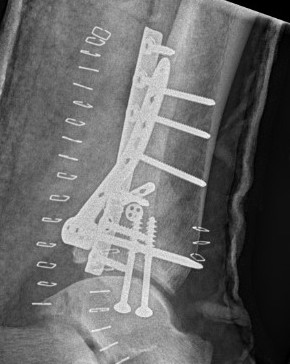

Operative management

Indications

1. Large fragment / ankle joint subluxation

2. Articular incongruency / articular step

3. Syndesmotic involvement

Dislocated ankle joint with large posterior malleolus

Articular incongruency

Posterior malleolus and syndesmotic injury

Fixation

Buttress plate

PA screws

Posterolateral buttress plate